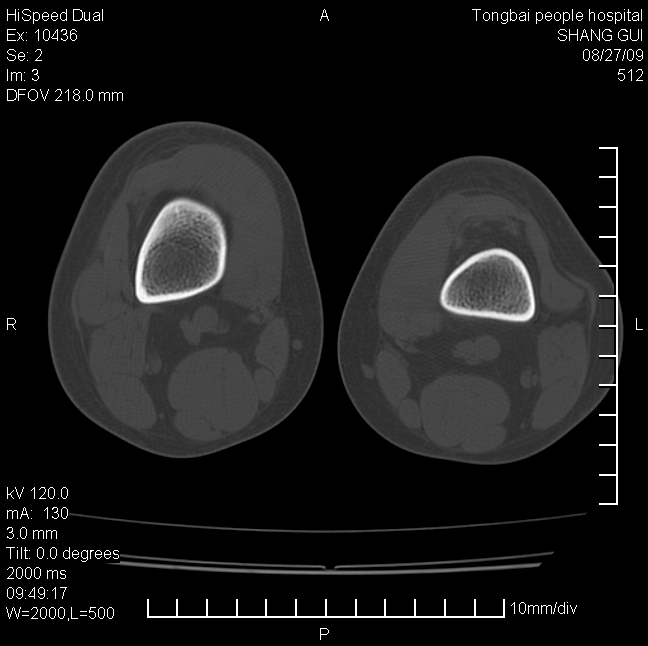

女,12岁。无意发现股骨下端隆起。局部皮肤颜色,温度无异常。

考虑右股骨下端骨纤维结构不良;不排除非骨化性纤维瘤。

不能排除,其实平片更直观。宽基底骨软骨瘤皮质与骨干皮质相连,髓腔与髓腔相通,骨纹理走行方向一致,部分软骨帽可有钙化,本例病变内“磨玻璃状、多囊状改变”比较符合骨纤。